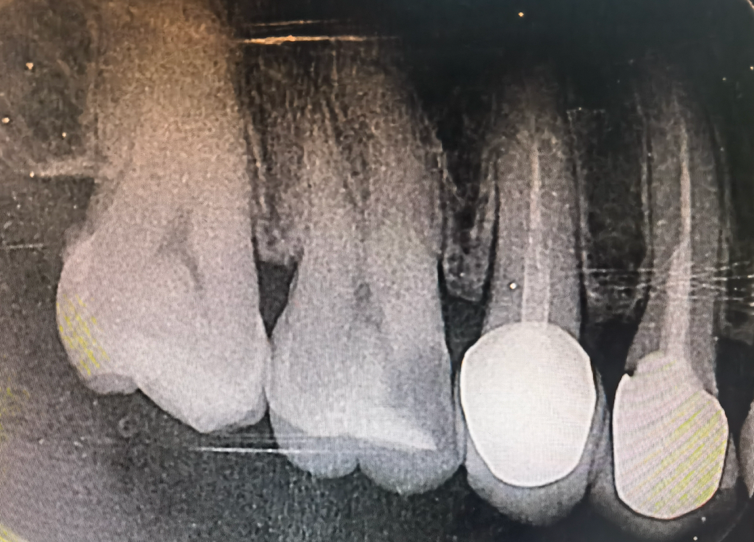

图片43.png

图3:一颗牙齿做窝沟封闭前后的对比图,直观显示封闭剂如何将深沟变浅、变平,从而易于清洁。